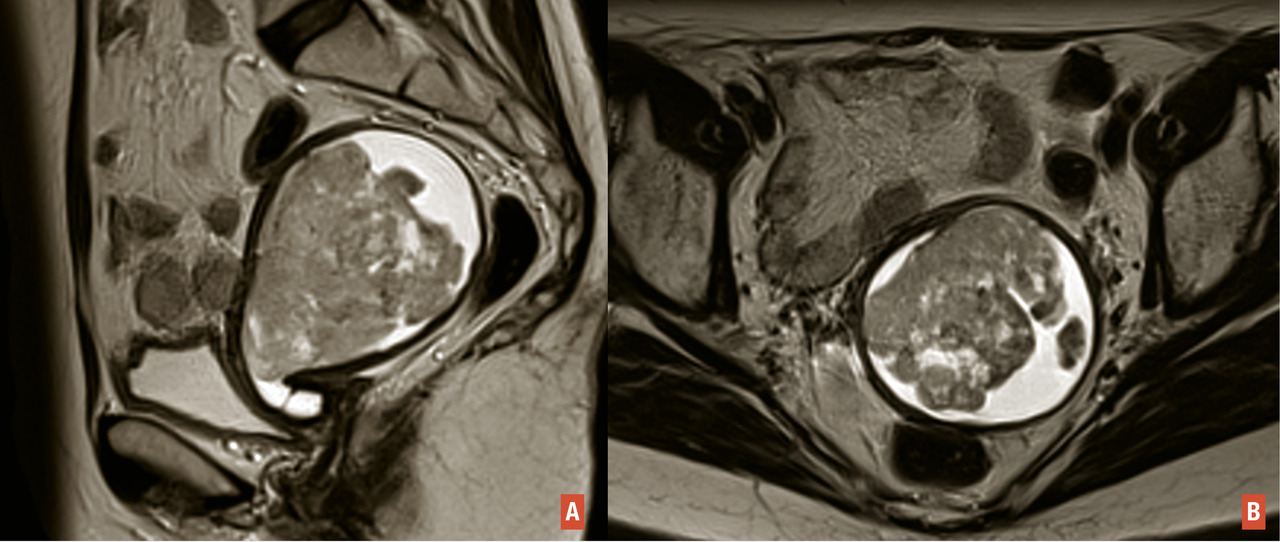

Les femmes porteuses de l’une de ces mutations sont à haut risque de cancer colorectal et de l’endomètre non endométrioïde [fig. 1 A et B], et à risque plus modéré de développer un cancer des ovaires (endométrioïdes ou à cellules claires) [fig. 2 A et B], de l’intestin grêle, des voies excrétrices urinaires, des voies biliaires et de l’estomac. Le spectre restreint regroupe les cancers du côlon, du rectum, de l’endomètre, de l’intestin grêle et des voies urinaires. Le spectre élargi inclut les autres types de cancer.